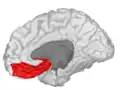

Orbital gyrus shown in red.

Medial surface of cerebral cortex - gyri

Basal surface of cerebrum. Orbital gyrus shown in red.